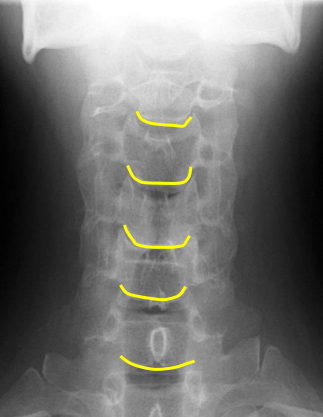

Inferior aspect of vertebral bodies

Junction of laminae

Pedicle shadows

Vertebral waist

Inferior endplate tips

Superior endplate tips

Disc spaces

End plate tips